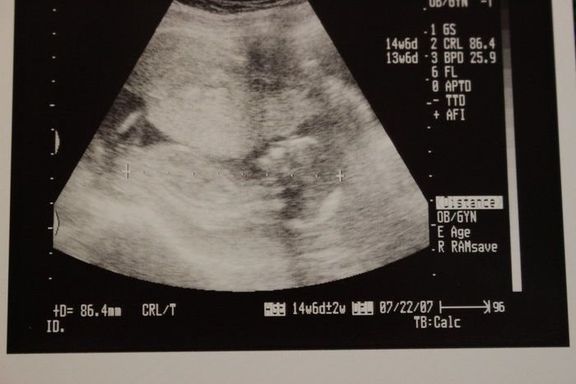

命の始まりは神秘的!2D・3D・4Dのエコー写真で見る「私と赤ちゃんの実録260日」 -

直前でまさかの性転換?みんなの予想を裏切り、ある日突然男の子になった我が子 -

エコー写真とともに綴る、愛しい我が子との“絆”を実感した妊娠期~ママと娘の265日~ -

エコー写真とともに綴る、愛しい我が子との“絆”を実感した妊娠期~ママと娘の265日~ -

緊急帝王切開で誕生。エコー写真で綴る息子と過ごした252日 -

緊急帝王切開で誕生。エコー写真で綴る息子と過ごした252日 -

不妊治療や2度の流産経験を経て「初めての出産」。日々成長する胎児の記録をエコー画像で振り返る -

待望の妊娠判明!エコー写真に見る、我が子を胸に抱くまでの“命の軌跡275日” -

エコー画像で振り返る、私に宿った小さな命が大きく育って誕生するまでの記録 -

推定体重は3773g!骨盤に入らず緊急帝王切開になった長女の成長をエコー写真で振り返る -

生まれる前からエコーを通して対面し、長女を少しずつお姉ちゃんにしてくれた次女の存在 -

生まれる前からエコーを通して対面し、長女を少しずつお姉ちゃんにしてくれた次女の存在